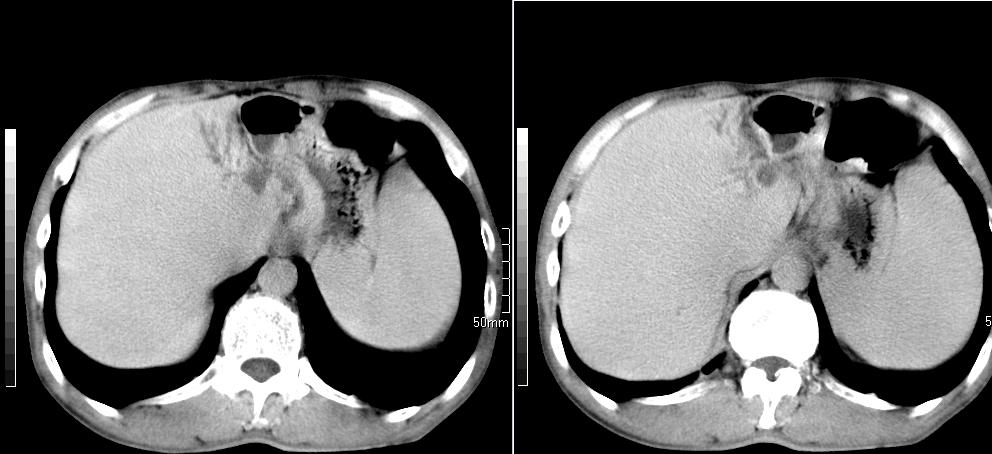

标题: CT26769:男,58岁,腹胀、腹部不适一年余 [打印本页]

标题: CT26769:男,58岁,腹胀、腹部不适一年余

1)考虑慢性胰腺炎并假性囊肿形成。2) 慢性胆囊炎。3)肝内胆管扩张。

1肝内胆管扩张,性质待定,2慢性胰腺炎胰管扩张,胰腺颈部假囊肿,3肝左叶低密度为小囊肿,4胆囊炎。

1)考虑慢性胰腺炎并假性囊肿形成。2)肝内胆管稍扩张。